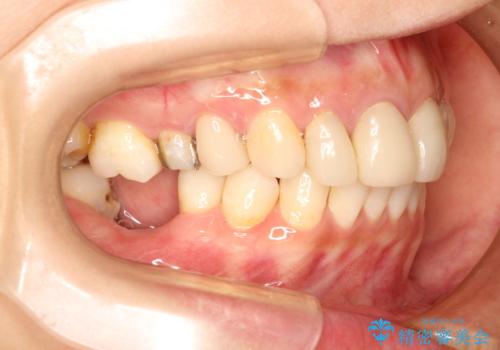

歯並びの改善とインプラントでのかみ合わせの回復 インプラント・セラミック・矯正全顎治療

- 歯医者が怖くて悪い歯をそのままにしてしまった、悪いところを治したいとのことで来院されました。

虫歯の歯や、歯を抜いてしまったところをそのまま放置していたことにより、歯並びも悪くなっていました。

矯正をはじめ、根の治療・インプラント・セラミックによる全体治療を提案させていただき、治療をしていくこととなりました。